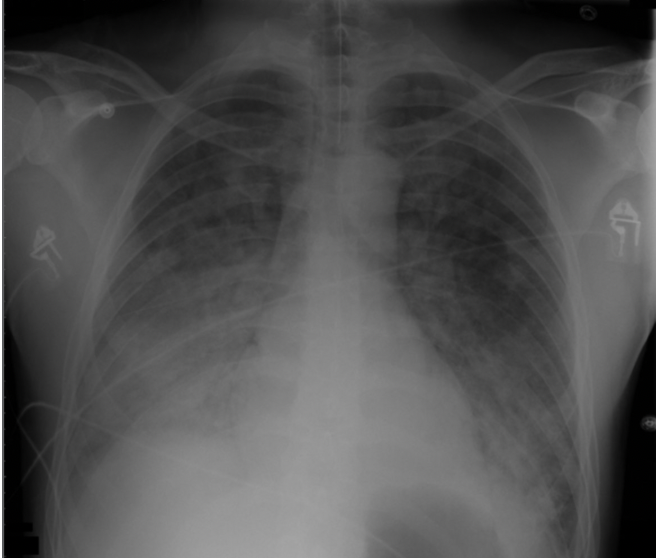

Which investigations would you do in a patient with suspected ARDS?